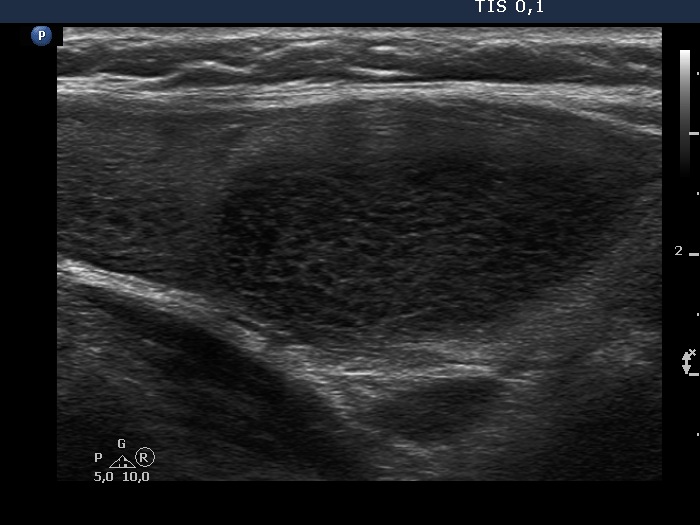

First examination (first, third and fifth rows of images):

Ultrasonography. The thyroid was echonormal and contained multiple inhomogeneous, partly blurred hypoechogenic and moderately hypoechogenic discrete lesions. Multiple lymph nodes were found on both sides of the neck.